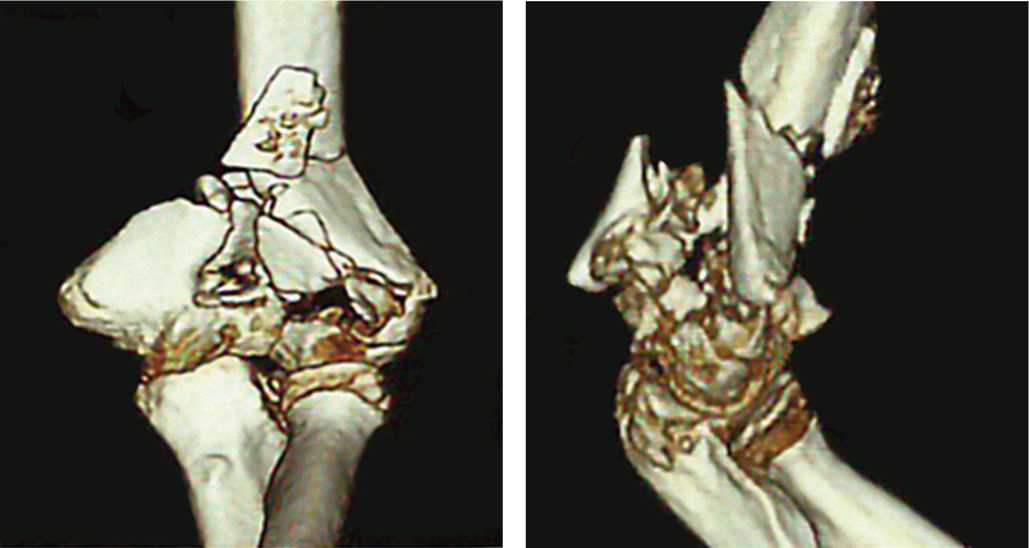

Чтобы проиллюстрировать последовательность применяемого нами алгоритма лечения, приведем пример пациентки У. (44 года), которая получила травму в результате дорожно-транспортного происшествия (диагноз: оскольчатый перелом левой плечевой кости в нижней трети со смещением отломков).

При поступлении в отделение назначен план обследования пациентки: анализы для выполнения анестезиологического пособия, электрокардиограмма, рентгенограммы грудной клетки, левого плеча (рис. 4), компьютерная томография правого плеча (рис. 5), консультация терапевта, невролога, анестезиолога-реаниматолога.

Рис. 5. Компьютерная томография дистального отдела левого плеча

Fig. 5. Computed tomography scan of the distal left shoulder